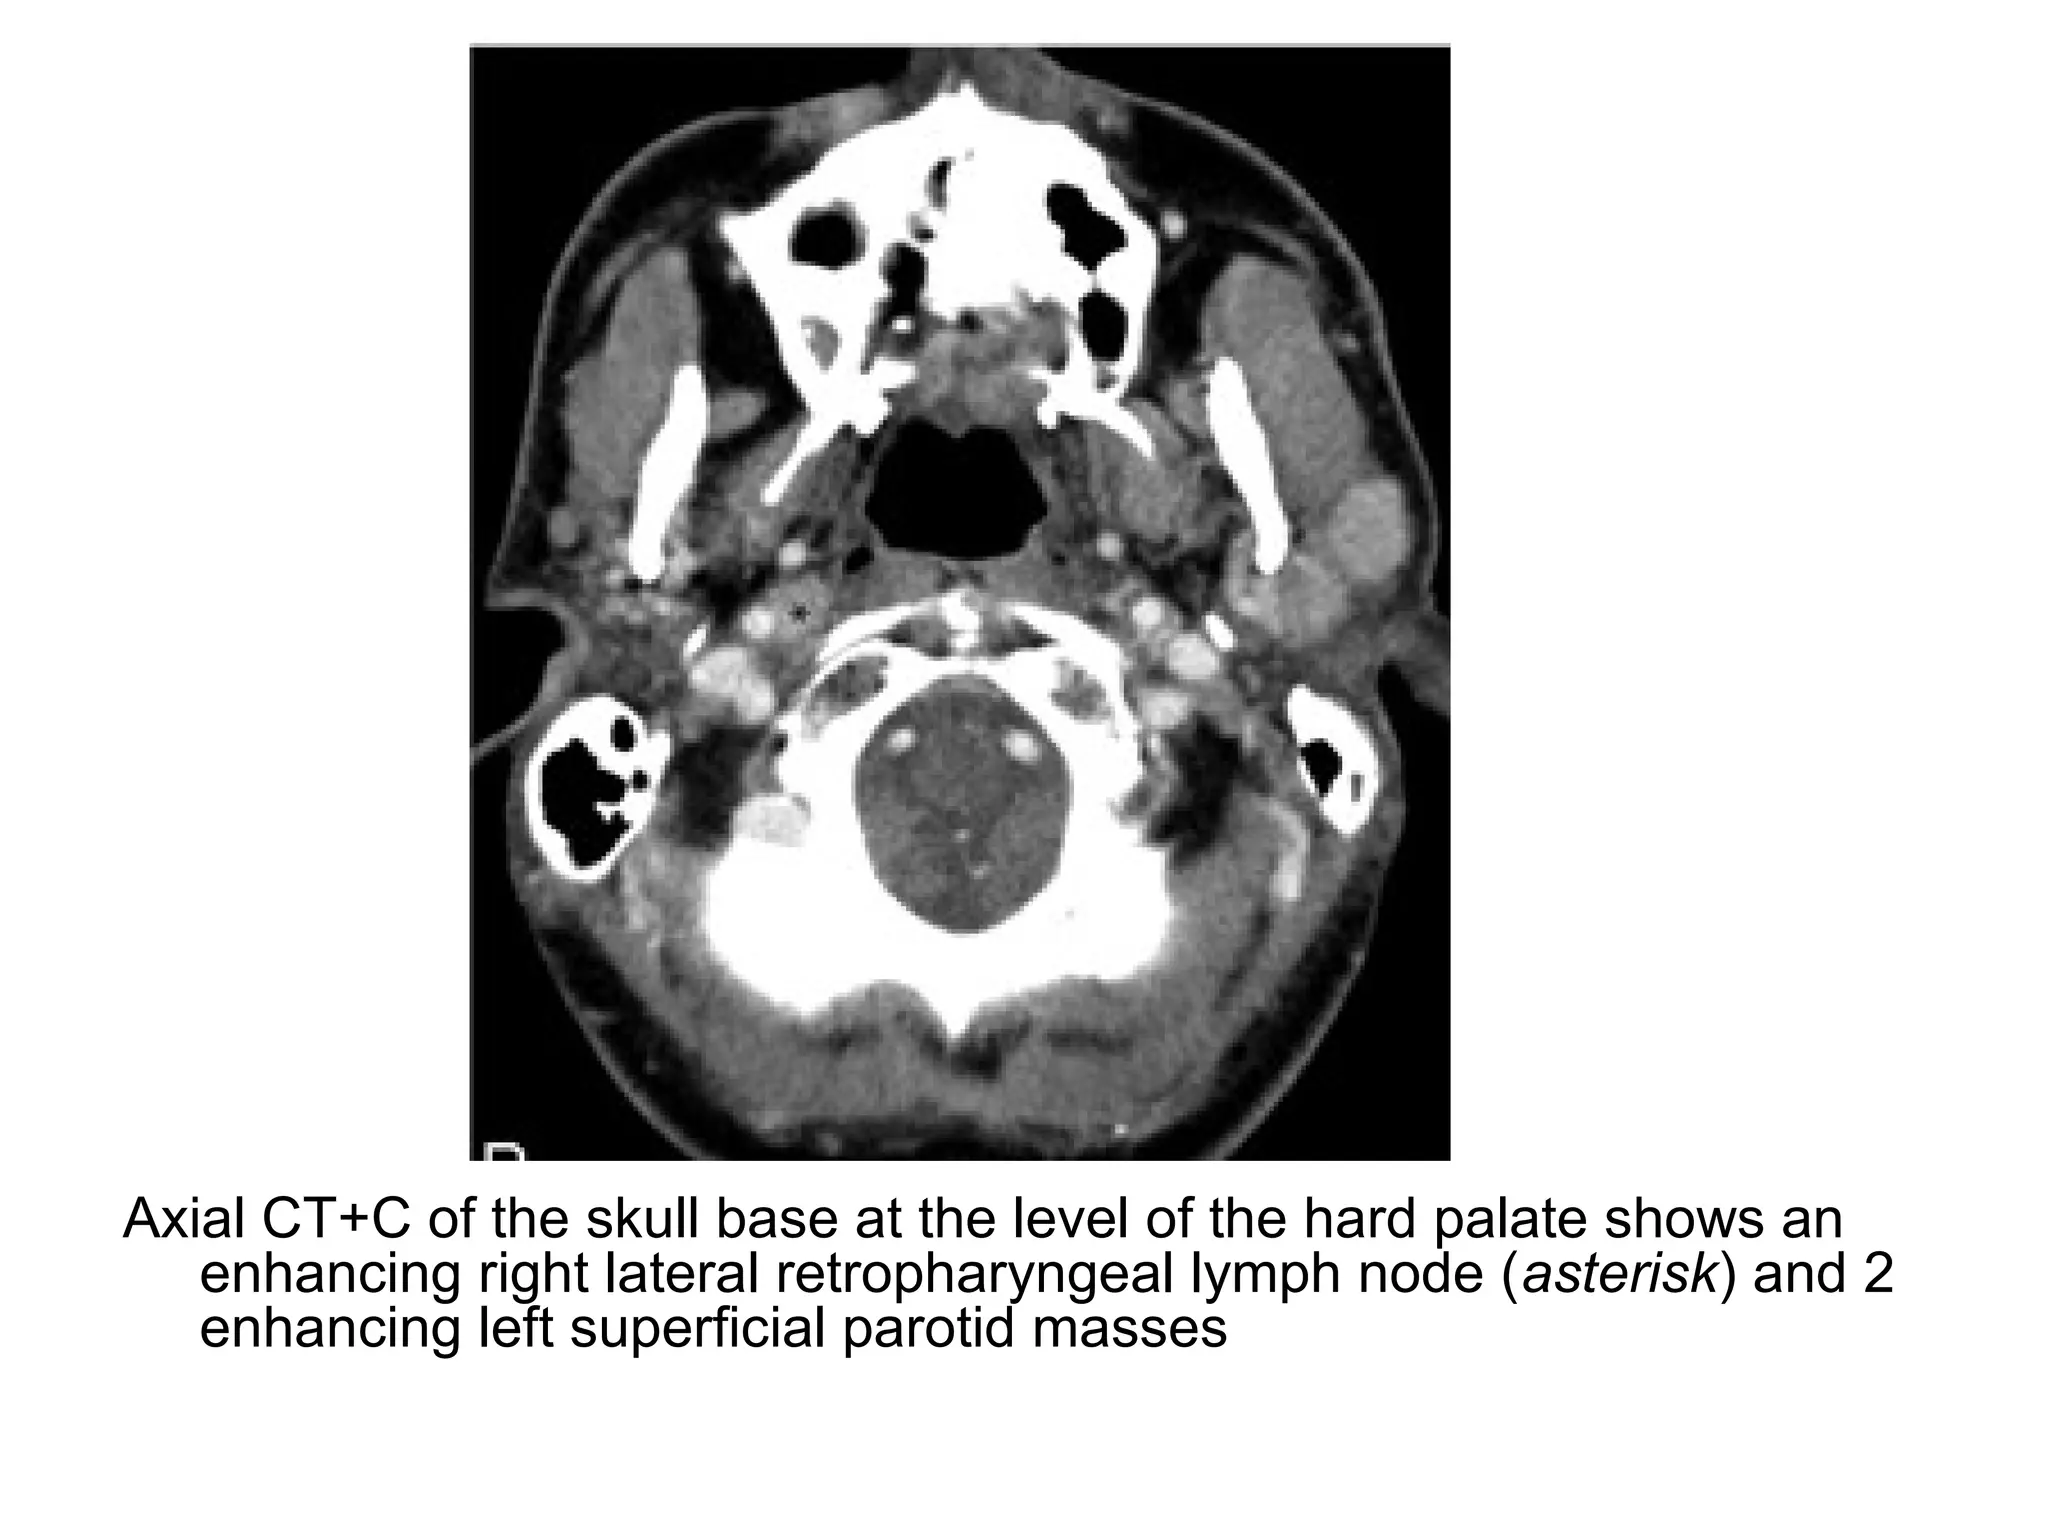

Axial CT+C of the skull base at the level of the hard palate shows an

enhancing right lateral retropharyngeal lymph node (asterisk) and 2

enhancing left superficial parotid masses